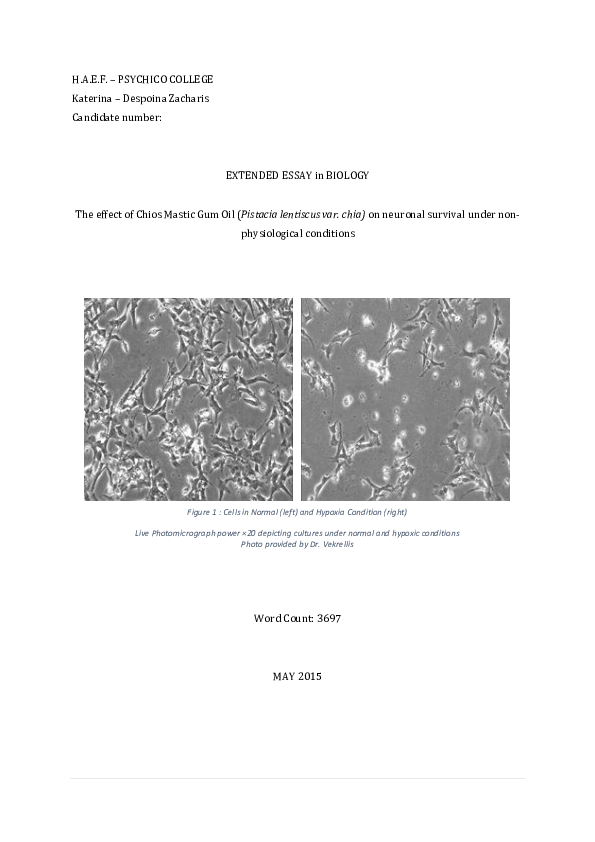

Design of pistacia lentiscus mastic gum biology essay image This picture demonstrates design of pistacia lentiscus mastic gum biology essay.

Phytochemical analysis and antioxidant and anticancer activities of mastic gum resin from pistacia atlantica subspecies kurdica heshu sulaiman rahman1-3 1department of clinic and internal medicine, college of veterinary medicine, university of sulaimani, sulaimani, kurdistan region, republic of iraq; 2department of medical laboratory sciences, college of science, komar university of science. Chia, so-called mastic gum, has been used to treat multiple conditions such as coughs, sore throats, eczema, dyslipidemia. Design of pistacia lentiscus mastic gum biology essay building design construction and performance specifications construction essay the average student has to read dozens of books per year. Design of pistacia lentiscus mastic gum biology essay the average student has to read dozens of books per year. The essential oil and gum of pistacia lentiscus var.